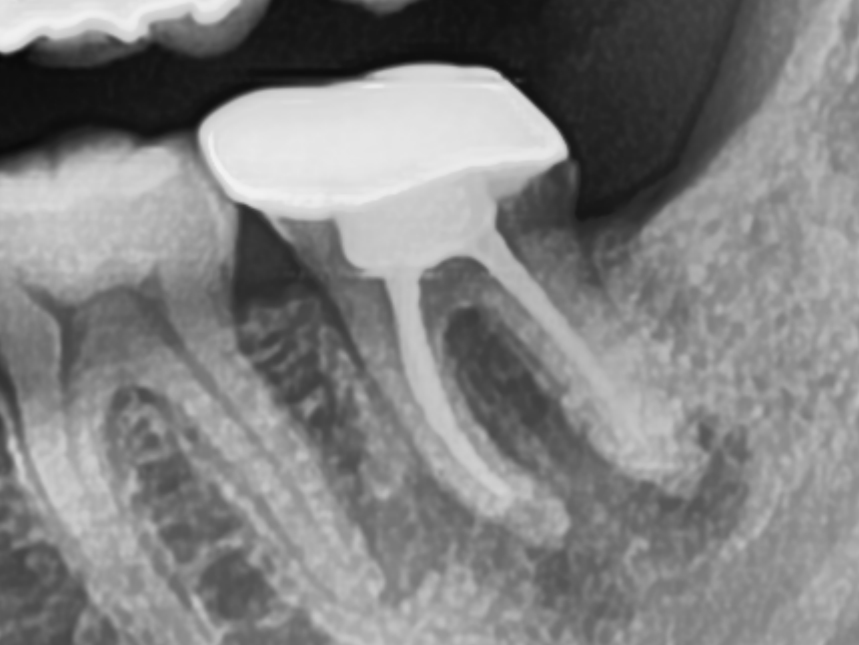

CASE.2 재신경치료

기존 신경치료 부분에 염증이 발생하여 재신경치료를 통해 치료치료전 2023.01.26 / 치료후 2023.02.27